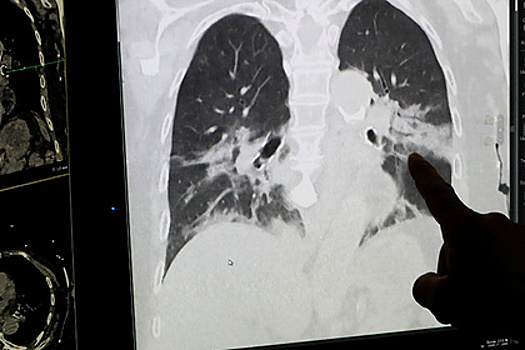

По данным издания, стволовые клетки способны предотвратить острую реакцию иммунной системы, которая приводит к острому респираторному дистресс-синдрому (ОРДС) — состоянию, когда легкие теряют способность насыщать кровь кислородом. Чрезмерная воспалительная реакция организма нарушает газообмен.

Ученые из Швеции нашли способ предотвращать это состояние. Он заключается в применении мезенхимальных стромальных клеток для лечения ОРДС. Эти клетки способны управлять работой иммунной системы.

Главврач больницы в Коммунарке Денис Проценко, которого цитирует издание, заявил, что более 80 процентов пациентов, зараженных коронавирусом, умирает именно от ОРДС. Это специфическая реакция организма на заражение коронавирусом — научного обоснования у этой особенности пока нет.